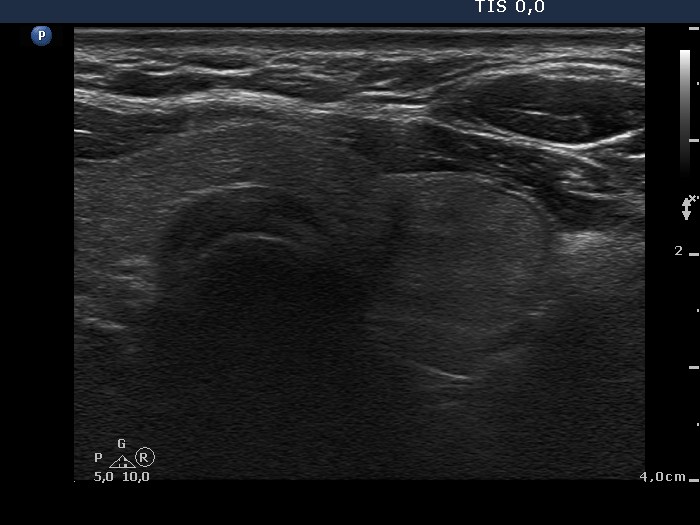

Consecutively operated patients with autoimmune thyroid disease - case 11 (conp 016) (ultrasonographic picture 7)

Left lobe, transverse scan. There is a minimally hypoechogenic nodule which presents halo sign.